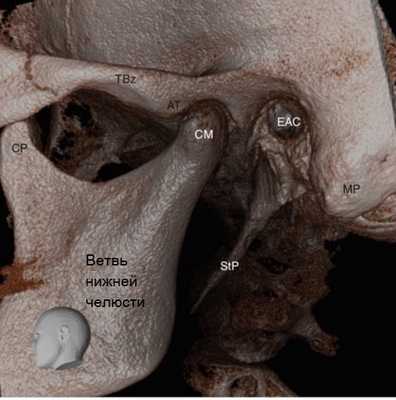

Рисунок 3 3D визуализация изображений конусно-лучевой компьютерной томографии левого височно-нижнечелюстного сустава у 62-летнего мужчины. АТ Суставной бугорок, СМ мыщелок нижней челюсти, СР венечный отросток, ЕАС наружный слуховой проход, МР сосцевидный отросток, StP шиловидный отросток, TBz скуловой отросток височной кости